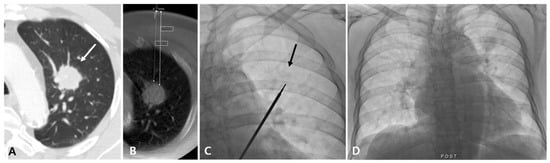

Figure 1.

Diagnostic failure of fluoroscopy-guided PTNB with the aid of planning CBCT for a lung nodule in a 78-year-old man with lung adenocarcinoma. A diagnostic CT image (A) and planning CBCT image (B) show a 28 mm nodule (white arrow) in the left upper lobe with a long lesion depth (85 mm, bold white dashed line). On fluoroscopy, the nodule is identifiable (black arrow) (C) and no immediate PTNB-related complications occurred (D). The pathologic specimen length of the lesion was 1 mm, and the pathology result was non-evaluable in this case.